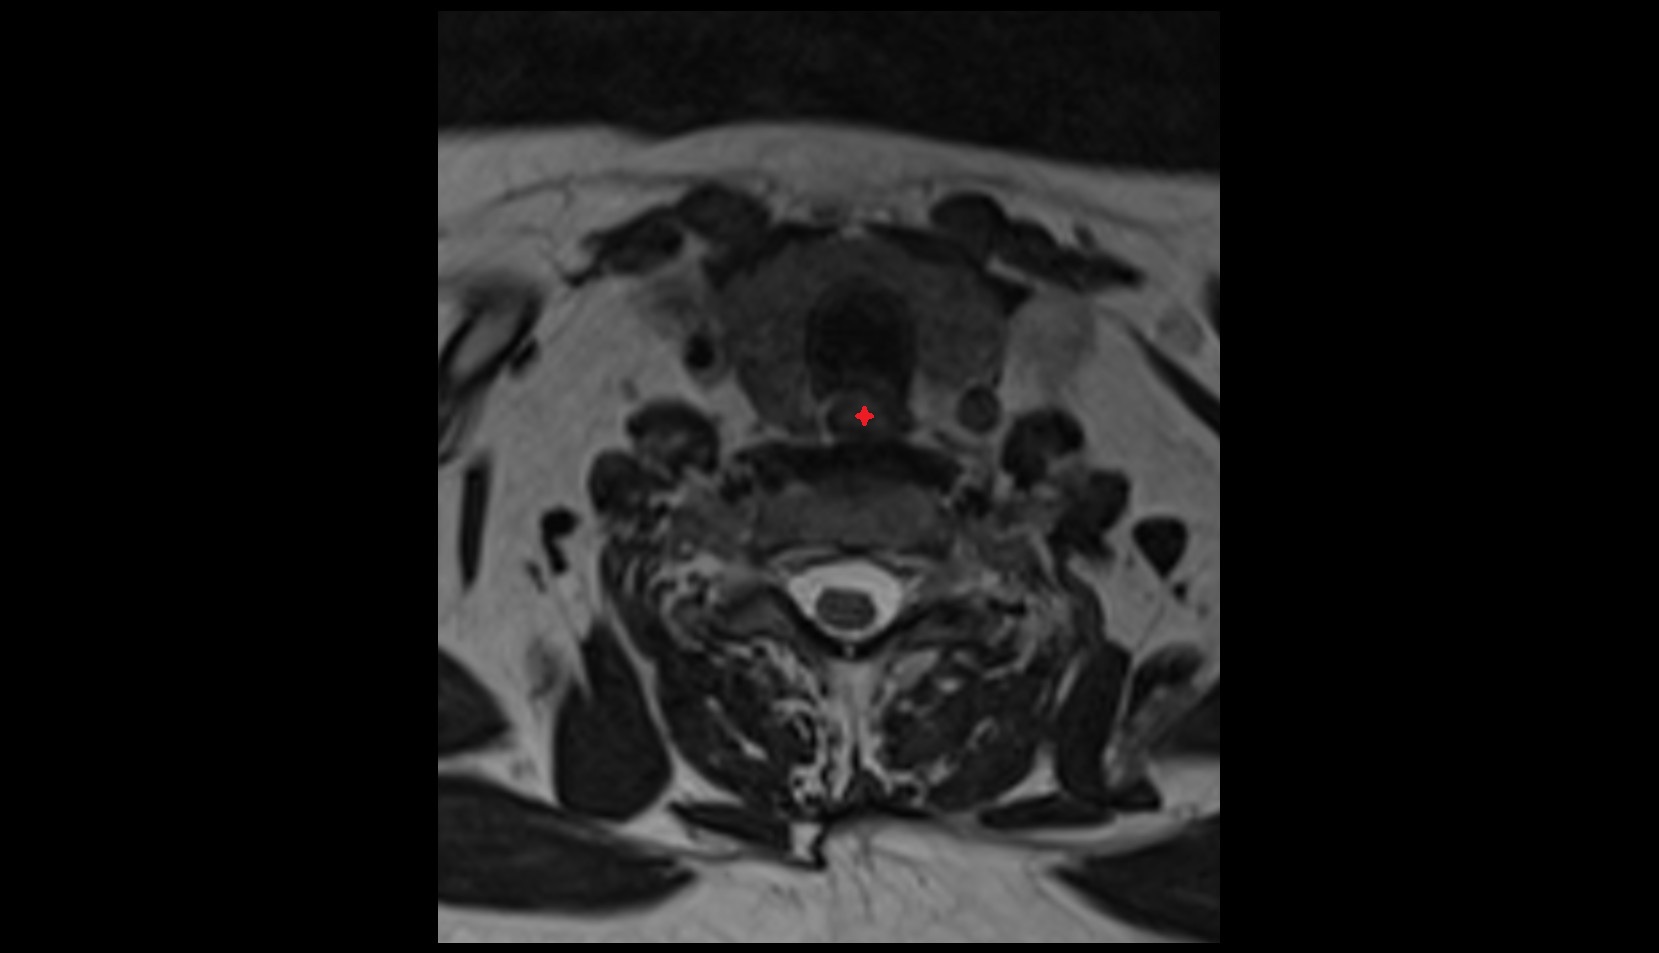

- Peripheral zone of prostate

- Anterior Fibromuscular Stroma of prostate

- Central zone of prostate

- Transitional zone of prostate